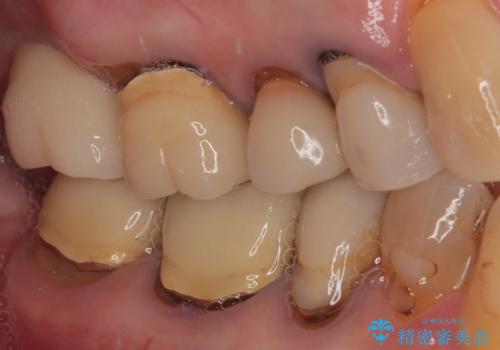

- 食事が取れないほどの激痛で、インプラント治療を希望して来院された患者様です。

近医にてクラウンを除去してもらった状態での来院でした。

遠心が歯根破折しており、歯槽骨が著しく吸収している状態であったため、抜歯即時でのインプラント埋入は断念し、2ヶ月ほど待機してから埋入することとしました。